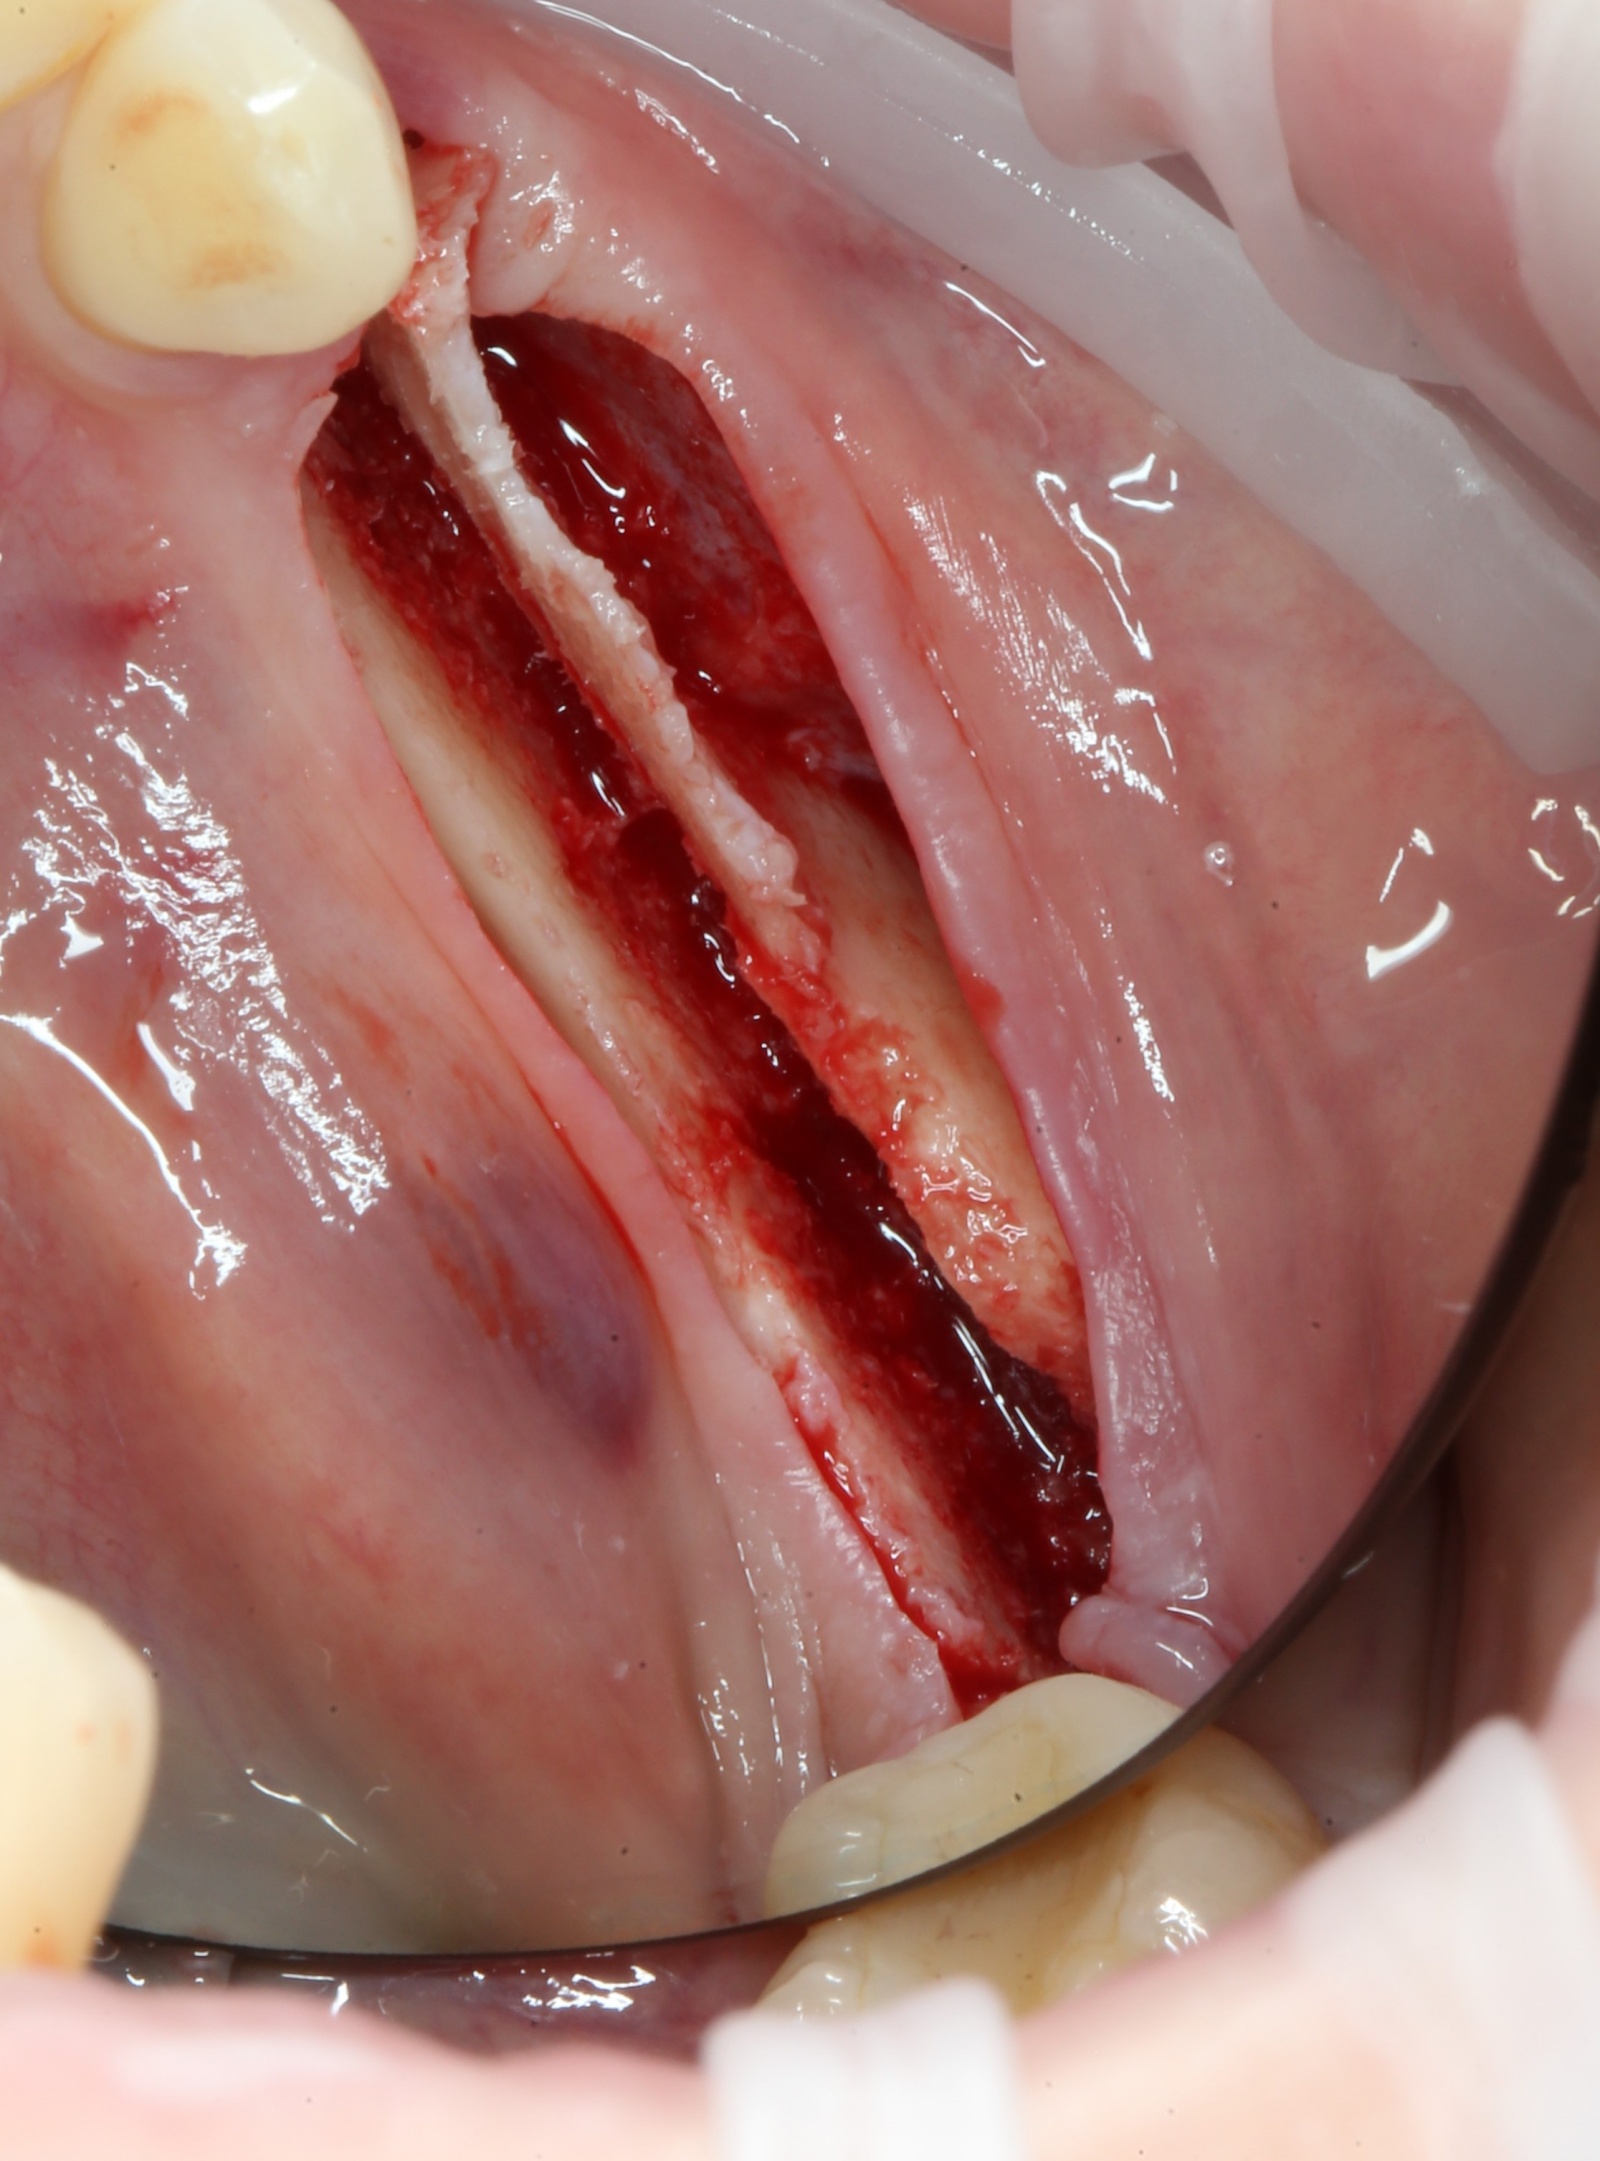

Вид сверху:

При помощи специальных остеотомов

аккуратнейшим образом производится «расклинивание» костных фрагментов. Почему аккуратнейшим? А потому, что костную стенку можно выломать, и вся операция может пойти по бороде.

Кость расщепили: